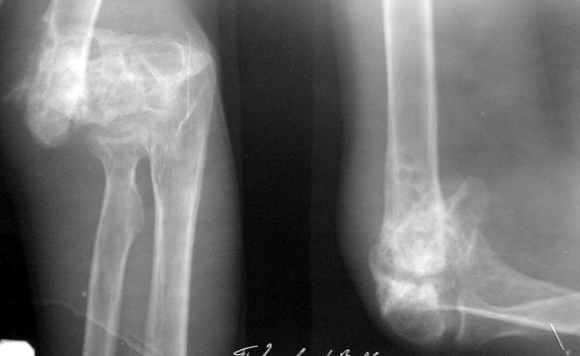

The recent x rays show established Non union with poor quality bone in the distal fragement. The joint is also appearing degenerate. In view of the multiple failed reconstructive surgeries, an Elbow replacement would seem reasonable.